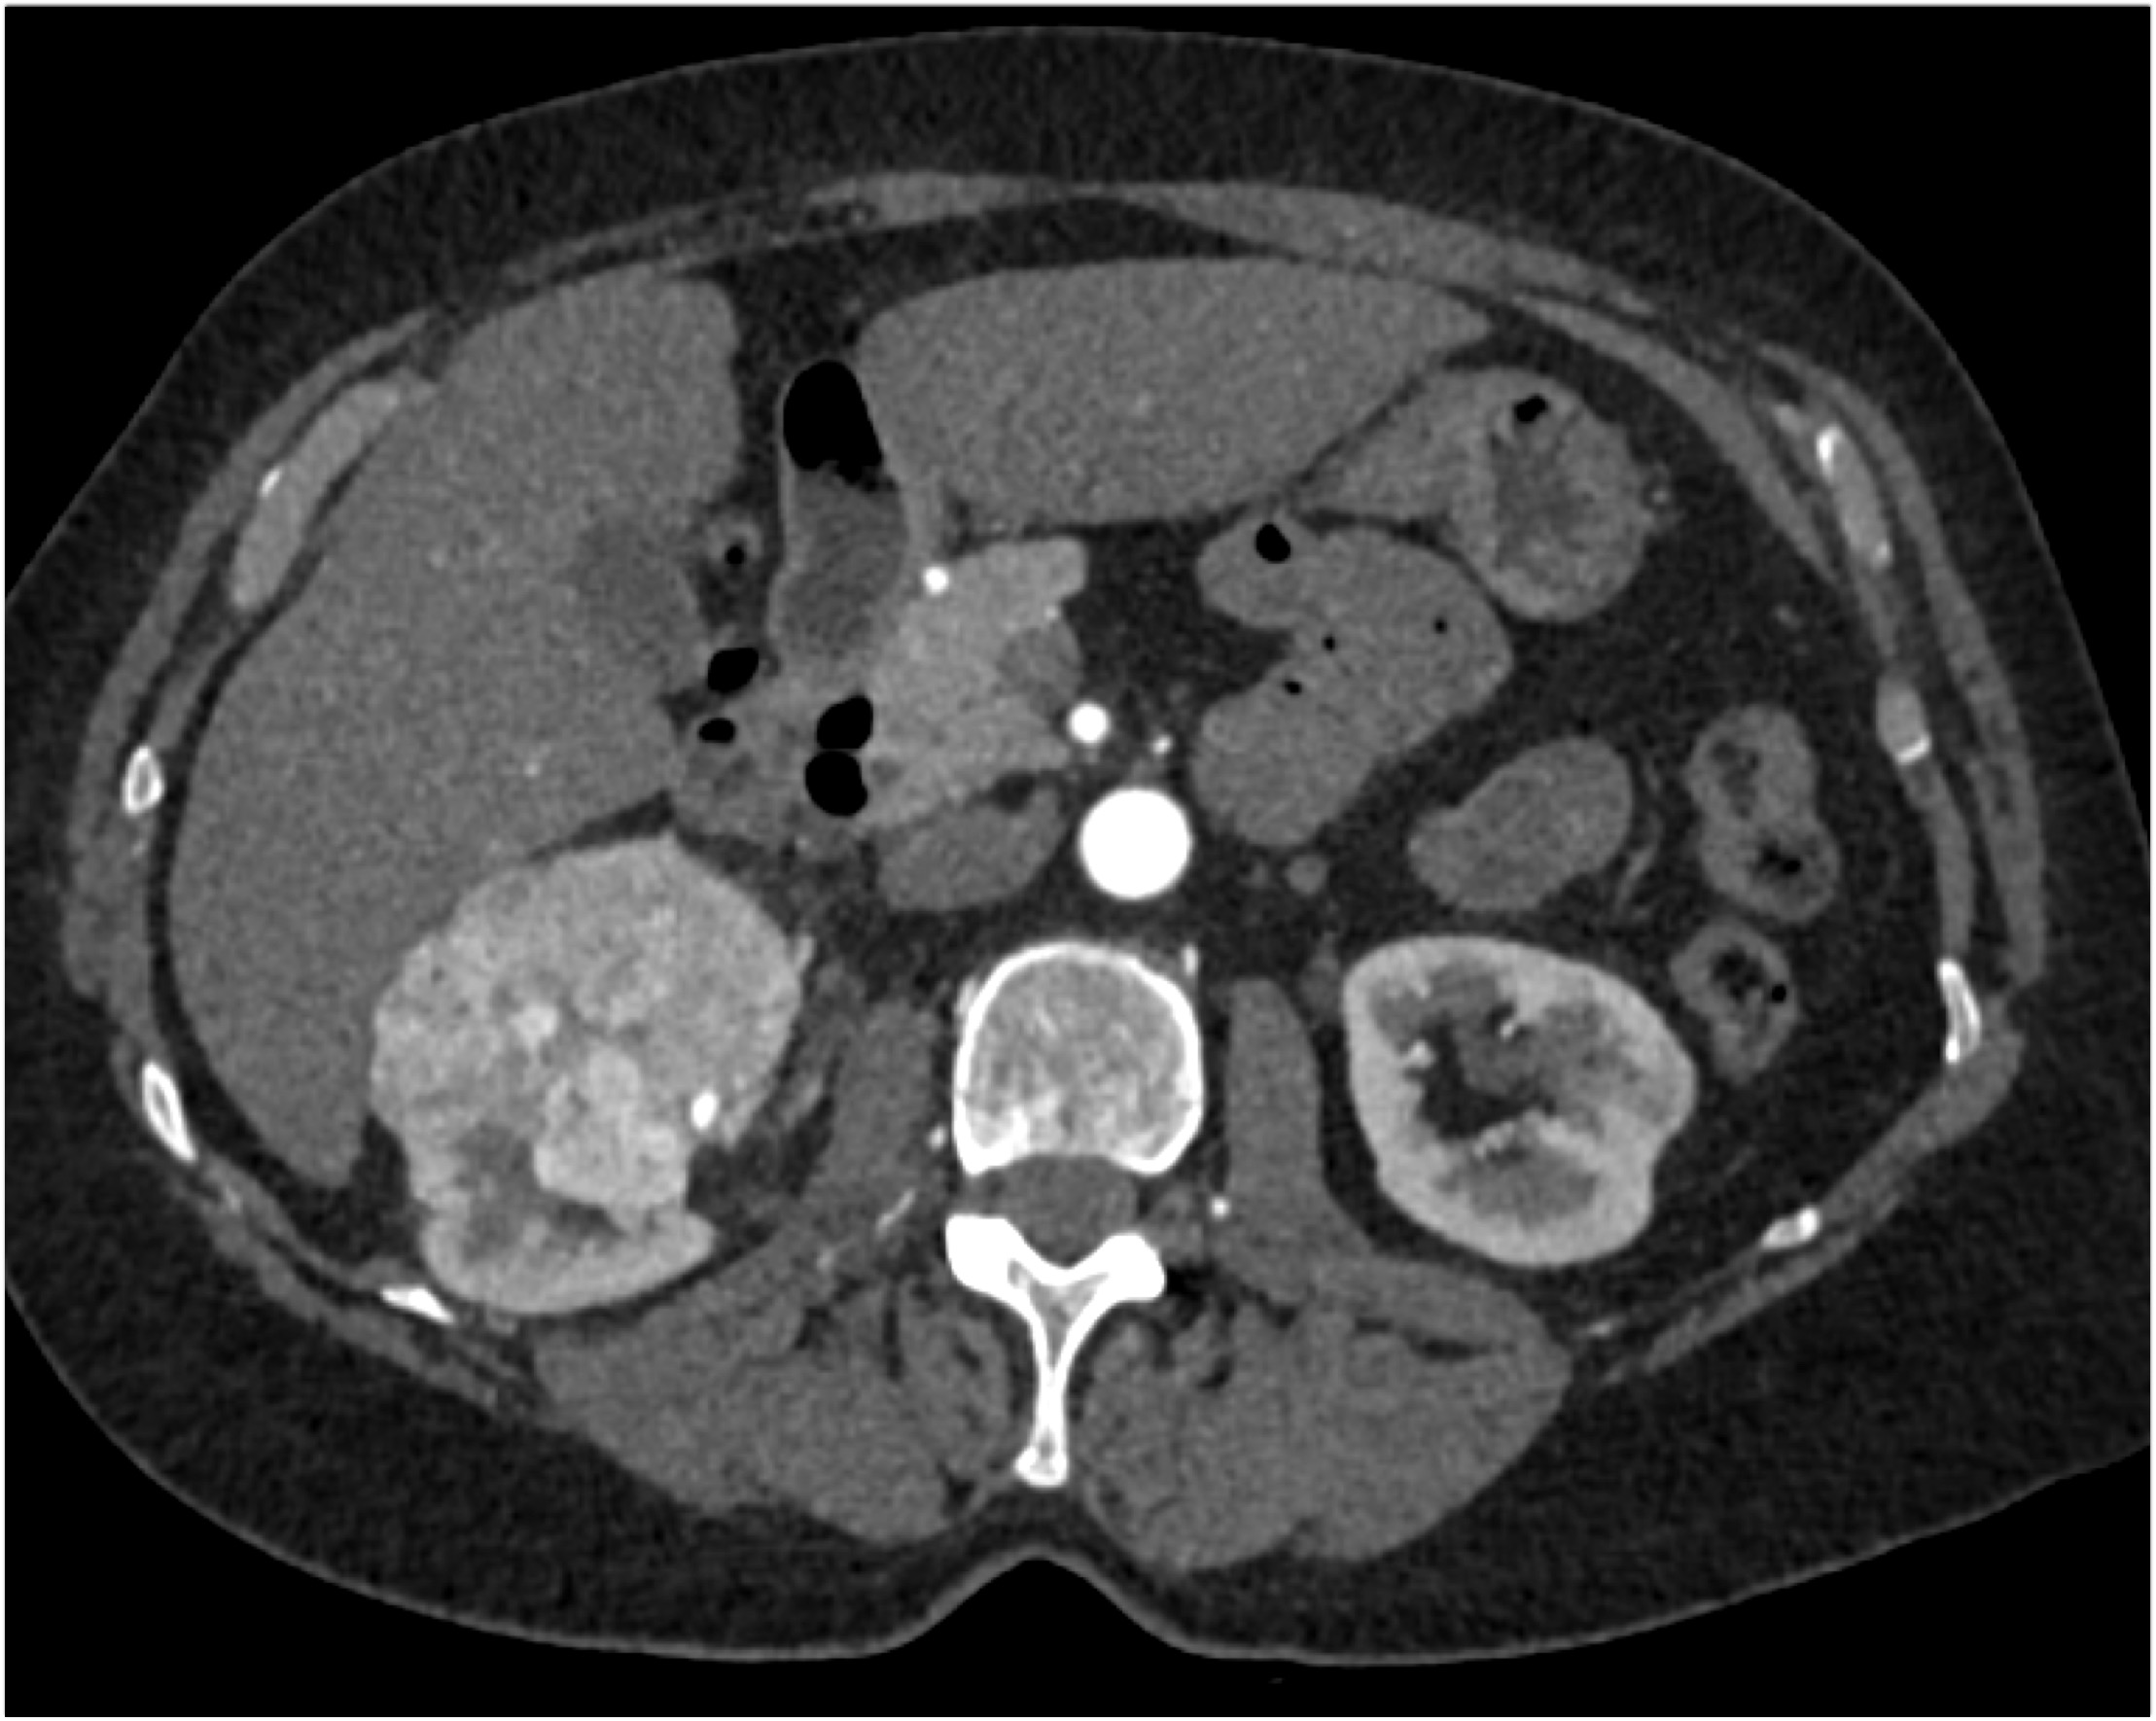

8) The least likely diagnosis in this case is

oncocytoma

papillary RCC

clear cell RCC

Bosniak 3 Cyst